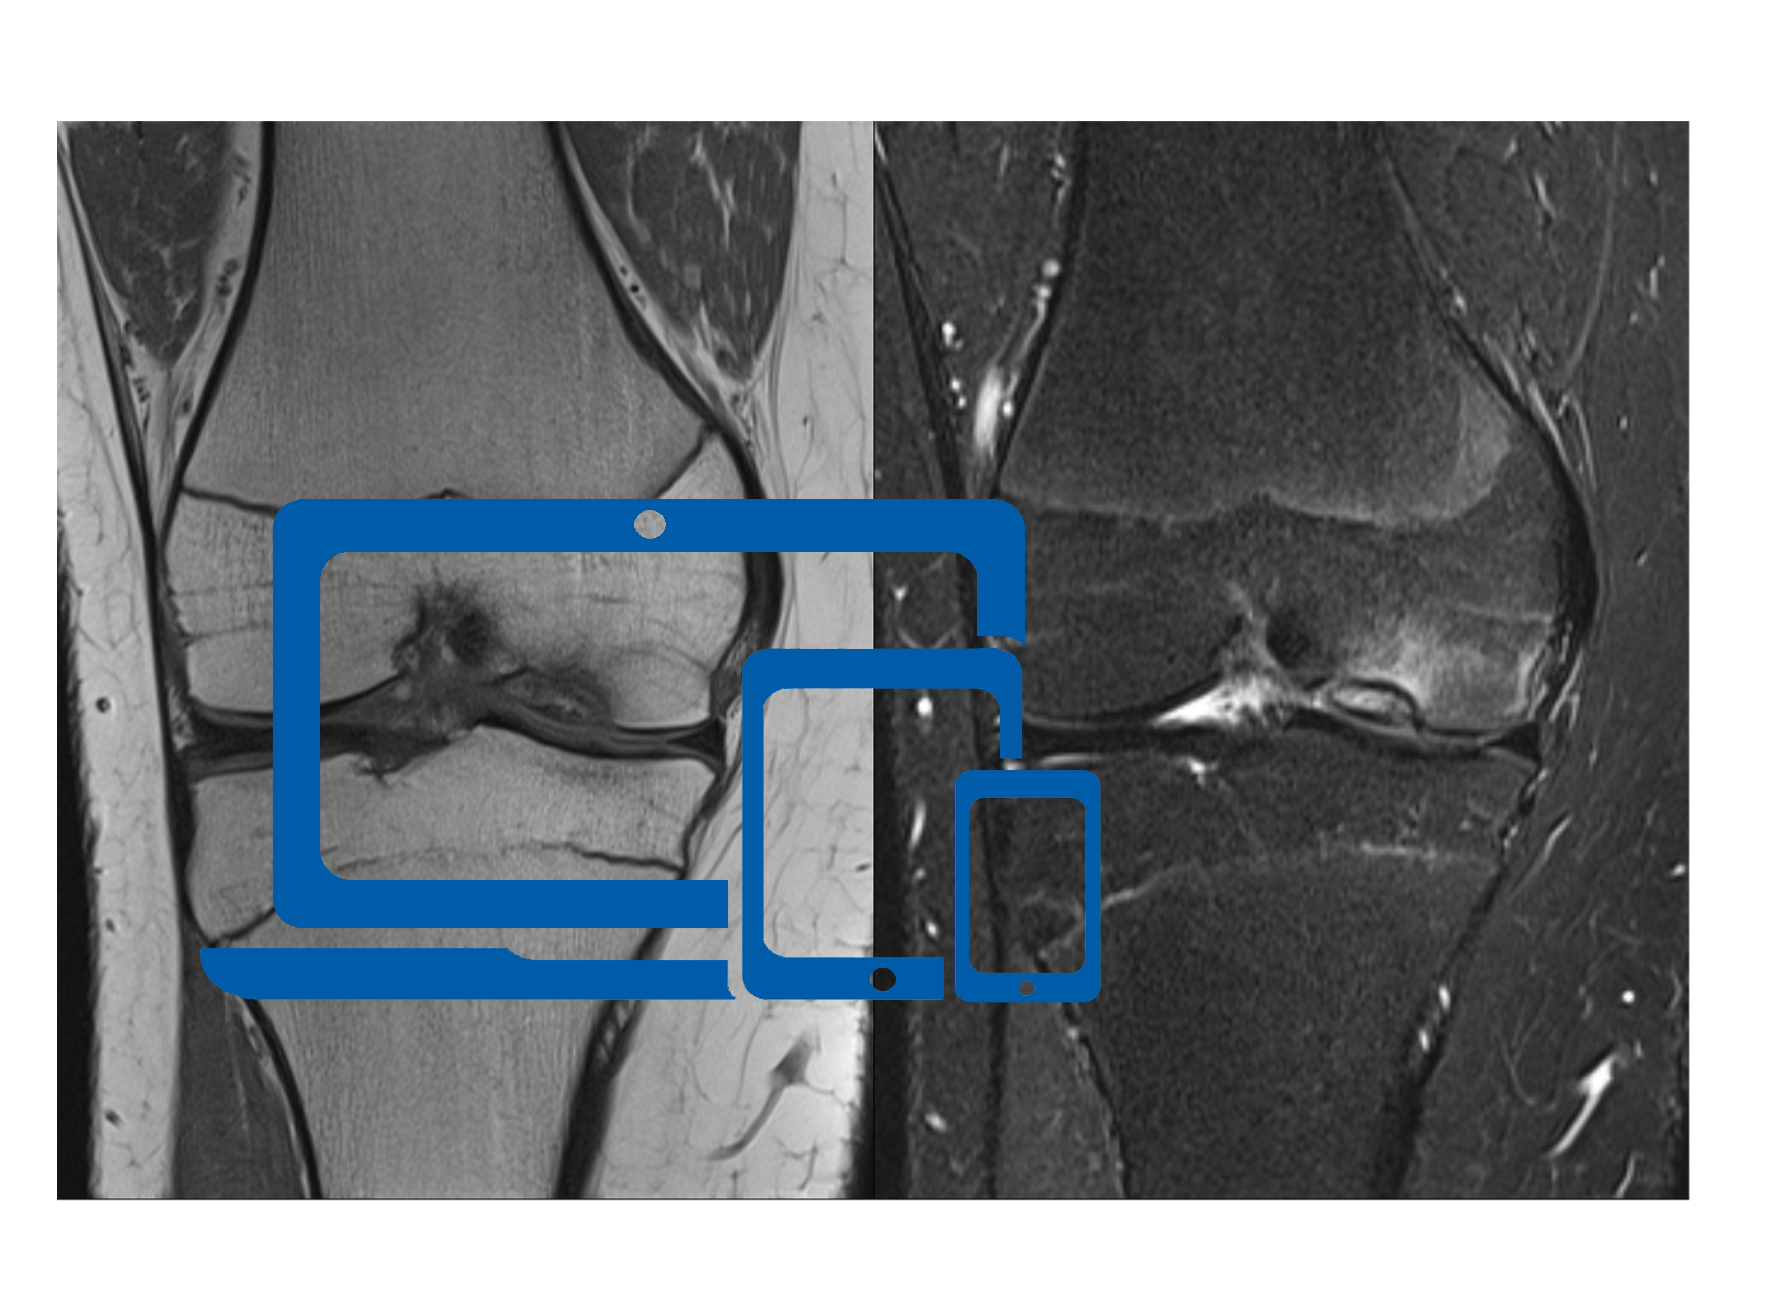

Elektronische Fälle als Bildschirmpräsentation

Knie - B. Fritz